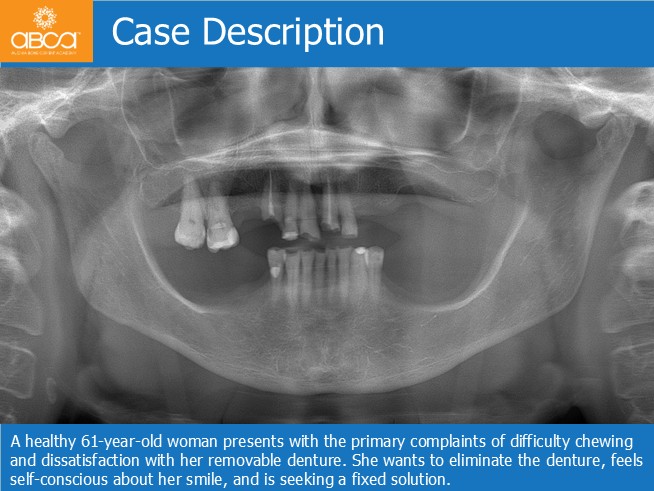

A healthy 61-year-old woman presents with the primary complaints of difficulty chewing and dissatisfaction with her removable denture. She wants to eliminate the denture, feels self-conscious about her smile, and is seeking a fixed solution.